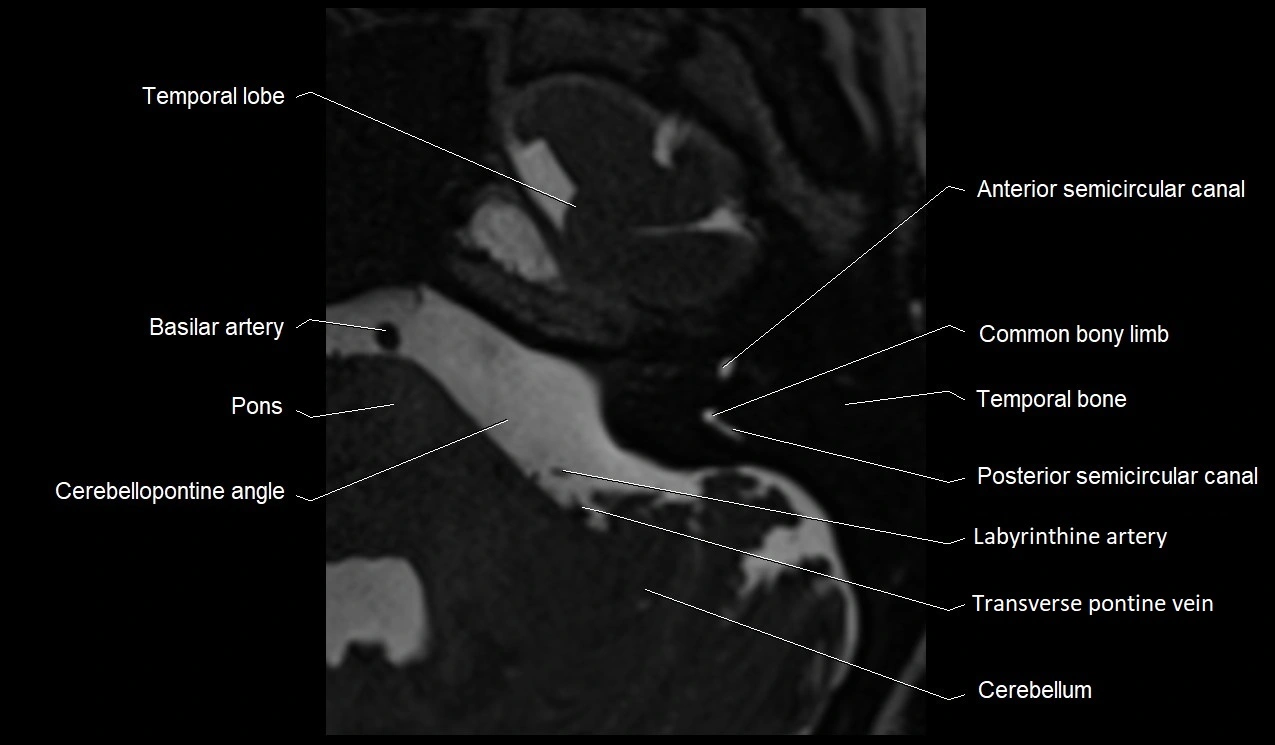

MRI Appearance

• The abducens nerve is a small, thin, linear structure

• Best visualized on high-resolution T2-weighted 3D MRI sequences (e.g., FIESTA or CISS)

• Seen as a hypointense (dark) line running from the brainstem at the pontomedullary junction, traversing the prepontine cistern, and entering Dorello’s canal under the petrosphenoidal ligament, then into the cavernous sinus, and finally the orbit

• May be challenging to visualize in standard MRI due to its small size

• Pathology may be inferred by absence, displacement, or enhancement of the nerve